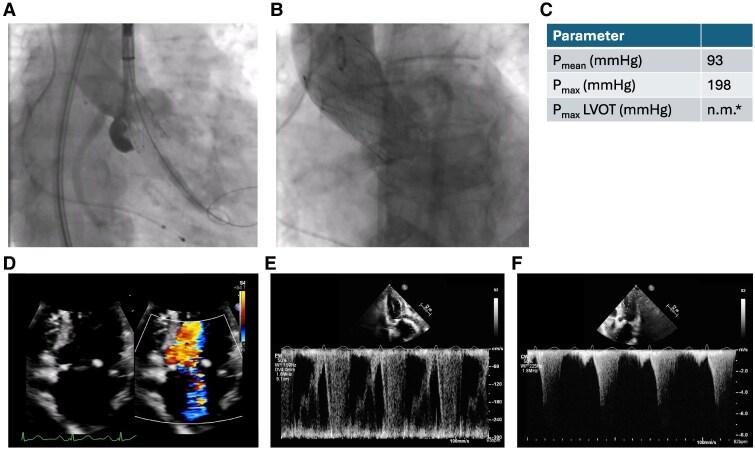

CASE SUMMARY

This case report presents an 88-year-old woman who developed severe LVOT obstruction following a successful transcatheter aortic valve implantation (TAVI), complicated by septal anterior motion of the mitral valve resulting in severe mitral regurgitation. Despite initial intensive care management, her symptoms persisted, necessitating the application of transcoronary ablation of septal hypertrophy as a bail-out procedure. Transcoronary ablation of septal hypertrophy, typically used in hypertrophic obstructive cardiomyopathy, successfully reduced the LVOT gradient and relieved symptoms.